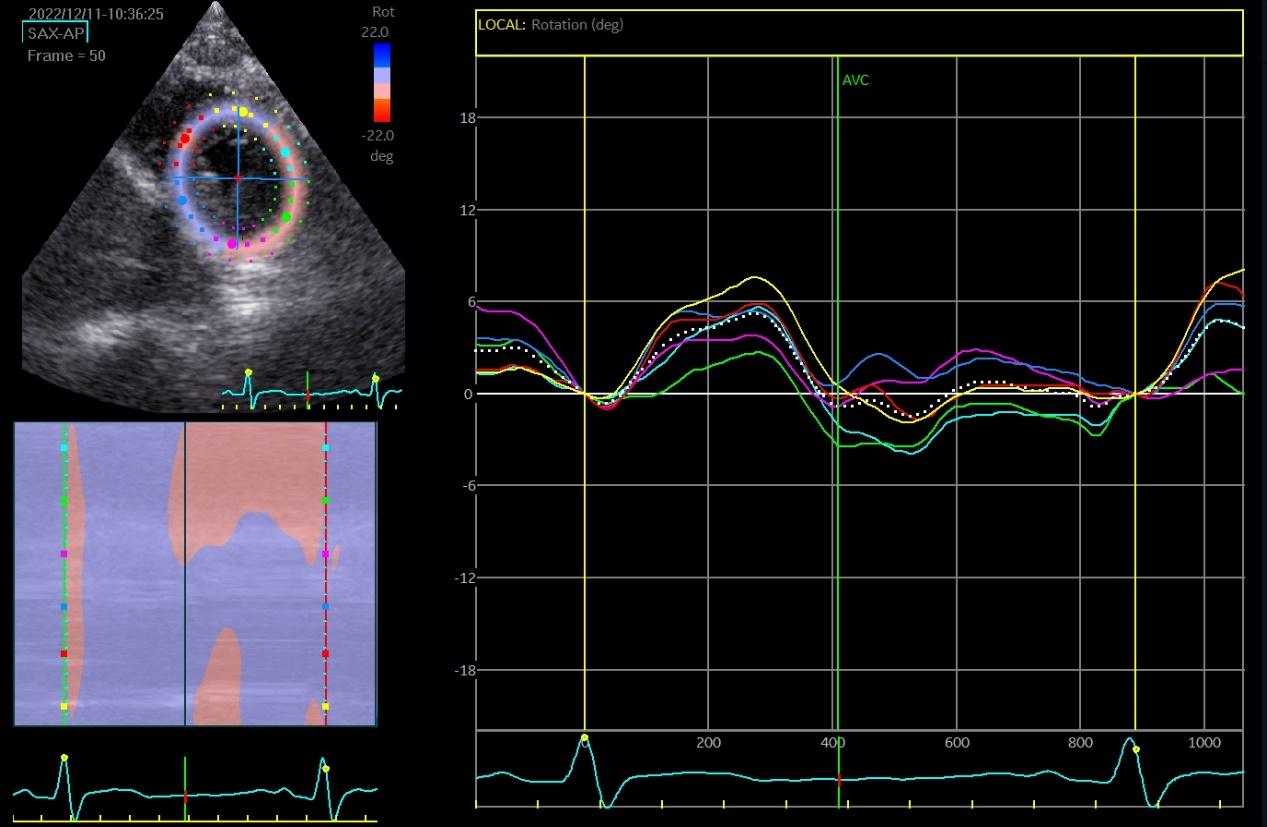

The speckle tracking echocardiographic data before and after the marathon are exhibited in Table 3. Before marathon (as baseline), the LT runners group showed significantly higher absolute values of apical rotation, LV twist, LV torsion and LV UTR, but a significantly lower absolute value of GLS, compared to the other groups (Table 3, p < 0.05). The GLS values were -19.39 ± 2.68, -21.56 ± 2.56, -21.04 ± 2.26 and -21.52 ± 2.35 in LT runners, ST runners, MET runners, and controls, respectively (Table 3). 1 hour after marathon, the absolute value of GCS was significantly lower in the LT runners group compared with the ST and MET runners (Table 3, p < 0.05). LV twist and LV torsion demonstrated similar trends across all 3 amateur marathon runners groups 1 hour after marathon, with no significant differences observed (Table 3, p > 0.05). Compared to baseline measurement, the absolute value of all speckle tracking echocardiographic parameters was decreased 1 hour after marathon in all amateur marathon runners (p < 0.05), and returned to baseline 4 days after marathon, showing no statistical differences before and 4 days after marathon (Table 3). Δ GLS, Δ GCS, Δ Apical rotation, Δ LV twist, Δ LV torsion, and Δ LV UTR were markedly elevated in the LT runners group relative to the ST runners and the MET runners groups (Table 4, p < 0.01). Basal rotation was similar in all 3 amateur marathon runners groups (Table 4). The apical rotation image and basal rotation image and left ventricular torsion diagram (speckle echocardiography) of the amateur marathon runners in the LT group can be seen in Figure 1-3.

Figure 1 Apical rotation image (speckle tracking echocardiographic) in LT group amateur marathon runners. LT, long-term.

Figure 2 Basal rotation image (speckle tracking echocardiographic) in LT group amateur marathon runners. LT, long-term.